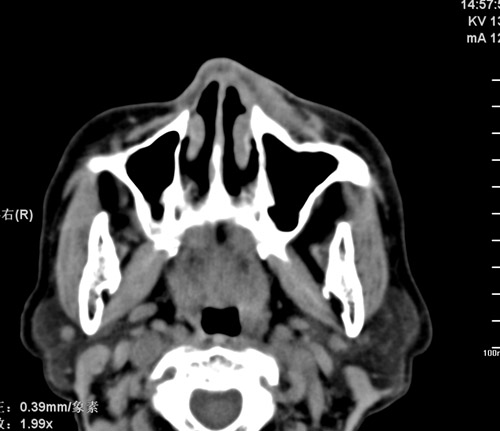

标题: CT17755:女,74 左鼻旁肿胀半年,临床以左上颌窦旁占位行CT [打印本页]

标题: CT17755:女,74 左鼻旁肿胀半年,临床以左上颌窦旁占位行CT

ct考虑鼻前庭囊肿 或鼻翼基底部慢性炎症,左上颌窦少许炎症 请指教

1)考虑左侧鼻前庭囊肿并感染。2)双侧上颌窦炎。

左侧鼻前庭囊肿并感染。双侧上颌窦炎。支持